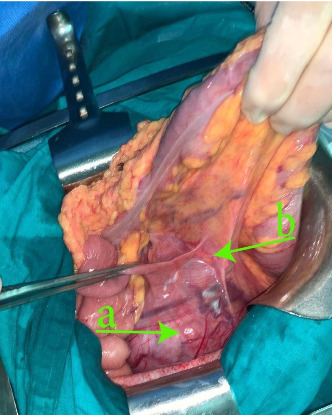

血管生成性平滑肌肉瘤(Angiogenic平滑肌肉瘤,LMS)是一种软组织肉瘤,主要发生在下腔静脉(IVC),超过50%的病例发生,肾静脉的LMS极为罕见。我们报告一例原发性左肾静脉LMS。病例报告:一名73岁女性,既往有高血压病史和左侧结肠腺癌,表现为间歇性左侧疼痛。影像学显示左侧主动脉外侧有一个大肿块。剖腹探查证实左肾门周围有多结节性肿瘤,需要行左肾全切除术。病理检查为2级LMS。患者术后恢复良好,无并发症。讨论:lms,尤其是血管源性lms,是一种罕见的侵袭性恶性肿瘤。尽管表现隐匿,但它们主要出现在女性身上,通常是成年人,而且经常出现在左侧。由于非特异性症状和影像学表现,诊断具有挑战性。手术切除仍然是治疗的基石,完全切除提供更好的结果。预后较差,特别是较大的肿瘤,部分切除和高度病变。辅助治疗的疗效尚不确定。结论:肾静脉LMS是一种罕见的疾病,诊断和治疗具有挑战性。根治性手术切除仍是主要治疗方法,但预后不佳,特别是在高危病例中。需要进一步的研究来优化这种罕见恶性肿瘤的治疗策略。

Introduction: Angiogenic leiomyosarcoma (LMS), a soft tissue sarcoma, primarily occurs in the inferior vena cava (IVC) in over 50% of cases, with renal vein LMSs being exceedingly rare. We present a case of primary LMS of the left renal vein. Case Report: A 73-year-old woman with a history of hypertension and prior left colon adenocarcinoma presented with intermittent left flank pain. Imaging revealed a large left latero-aortic mass. Exploratory laparotomy confirmed a multinodular tumor around the left renal hilum, necessitating en bloc resection with left nephrectomy. Pathological examination identified it as a grade 2 LMS. The patient recovered well postoperatively with no complications. Discussion: LMSs, especially of vascular origin, are rare and aggressive malignancies. Despite their insidious presentation, they predominantly manifest in women, typically adults, and often on the left side. Diagnosis is challenging due to nonspecific symptoms and imaging findings. Surgical resection remains the cornerstone of treatment, with complete resection offering better outcomes. Prognosis is poor, particularly with larger tumors, partial resection, and high-grade lesions. Adjuvant therapy's efficacy is uncertain. Conclusion: LMS of the renal vein is a rare entity with challenging diagnosis and management. Radical surgical resection remains the mainstay, but prognosis is guarded, especially in high-risk cases. Further research is needed to optimize treatment strategies for this rare malignancy.